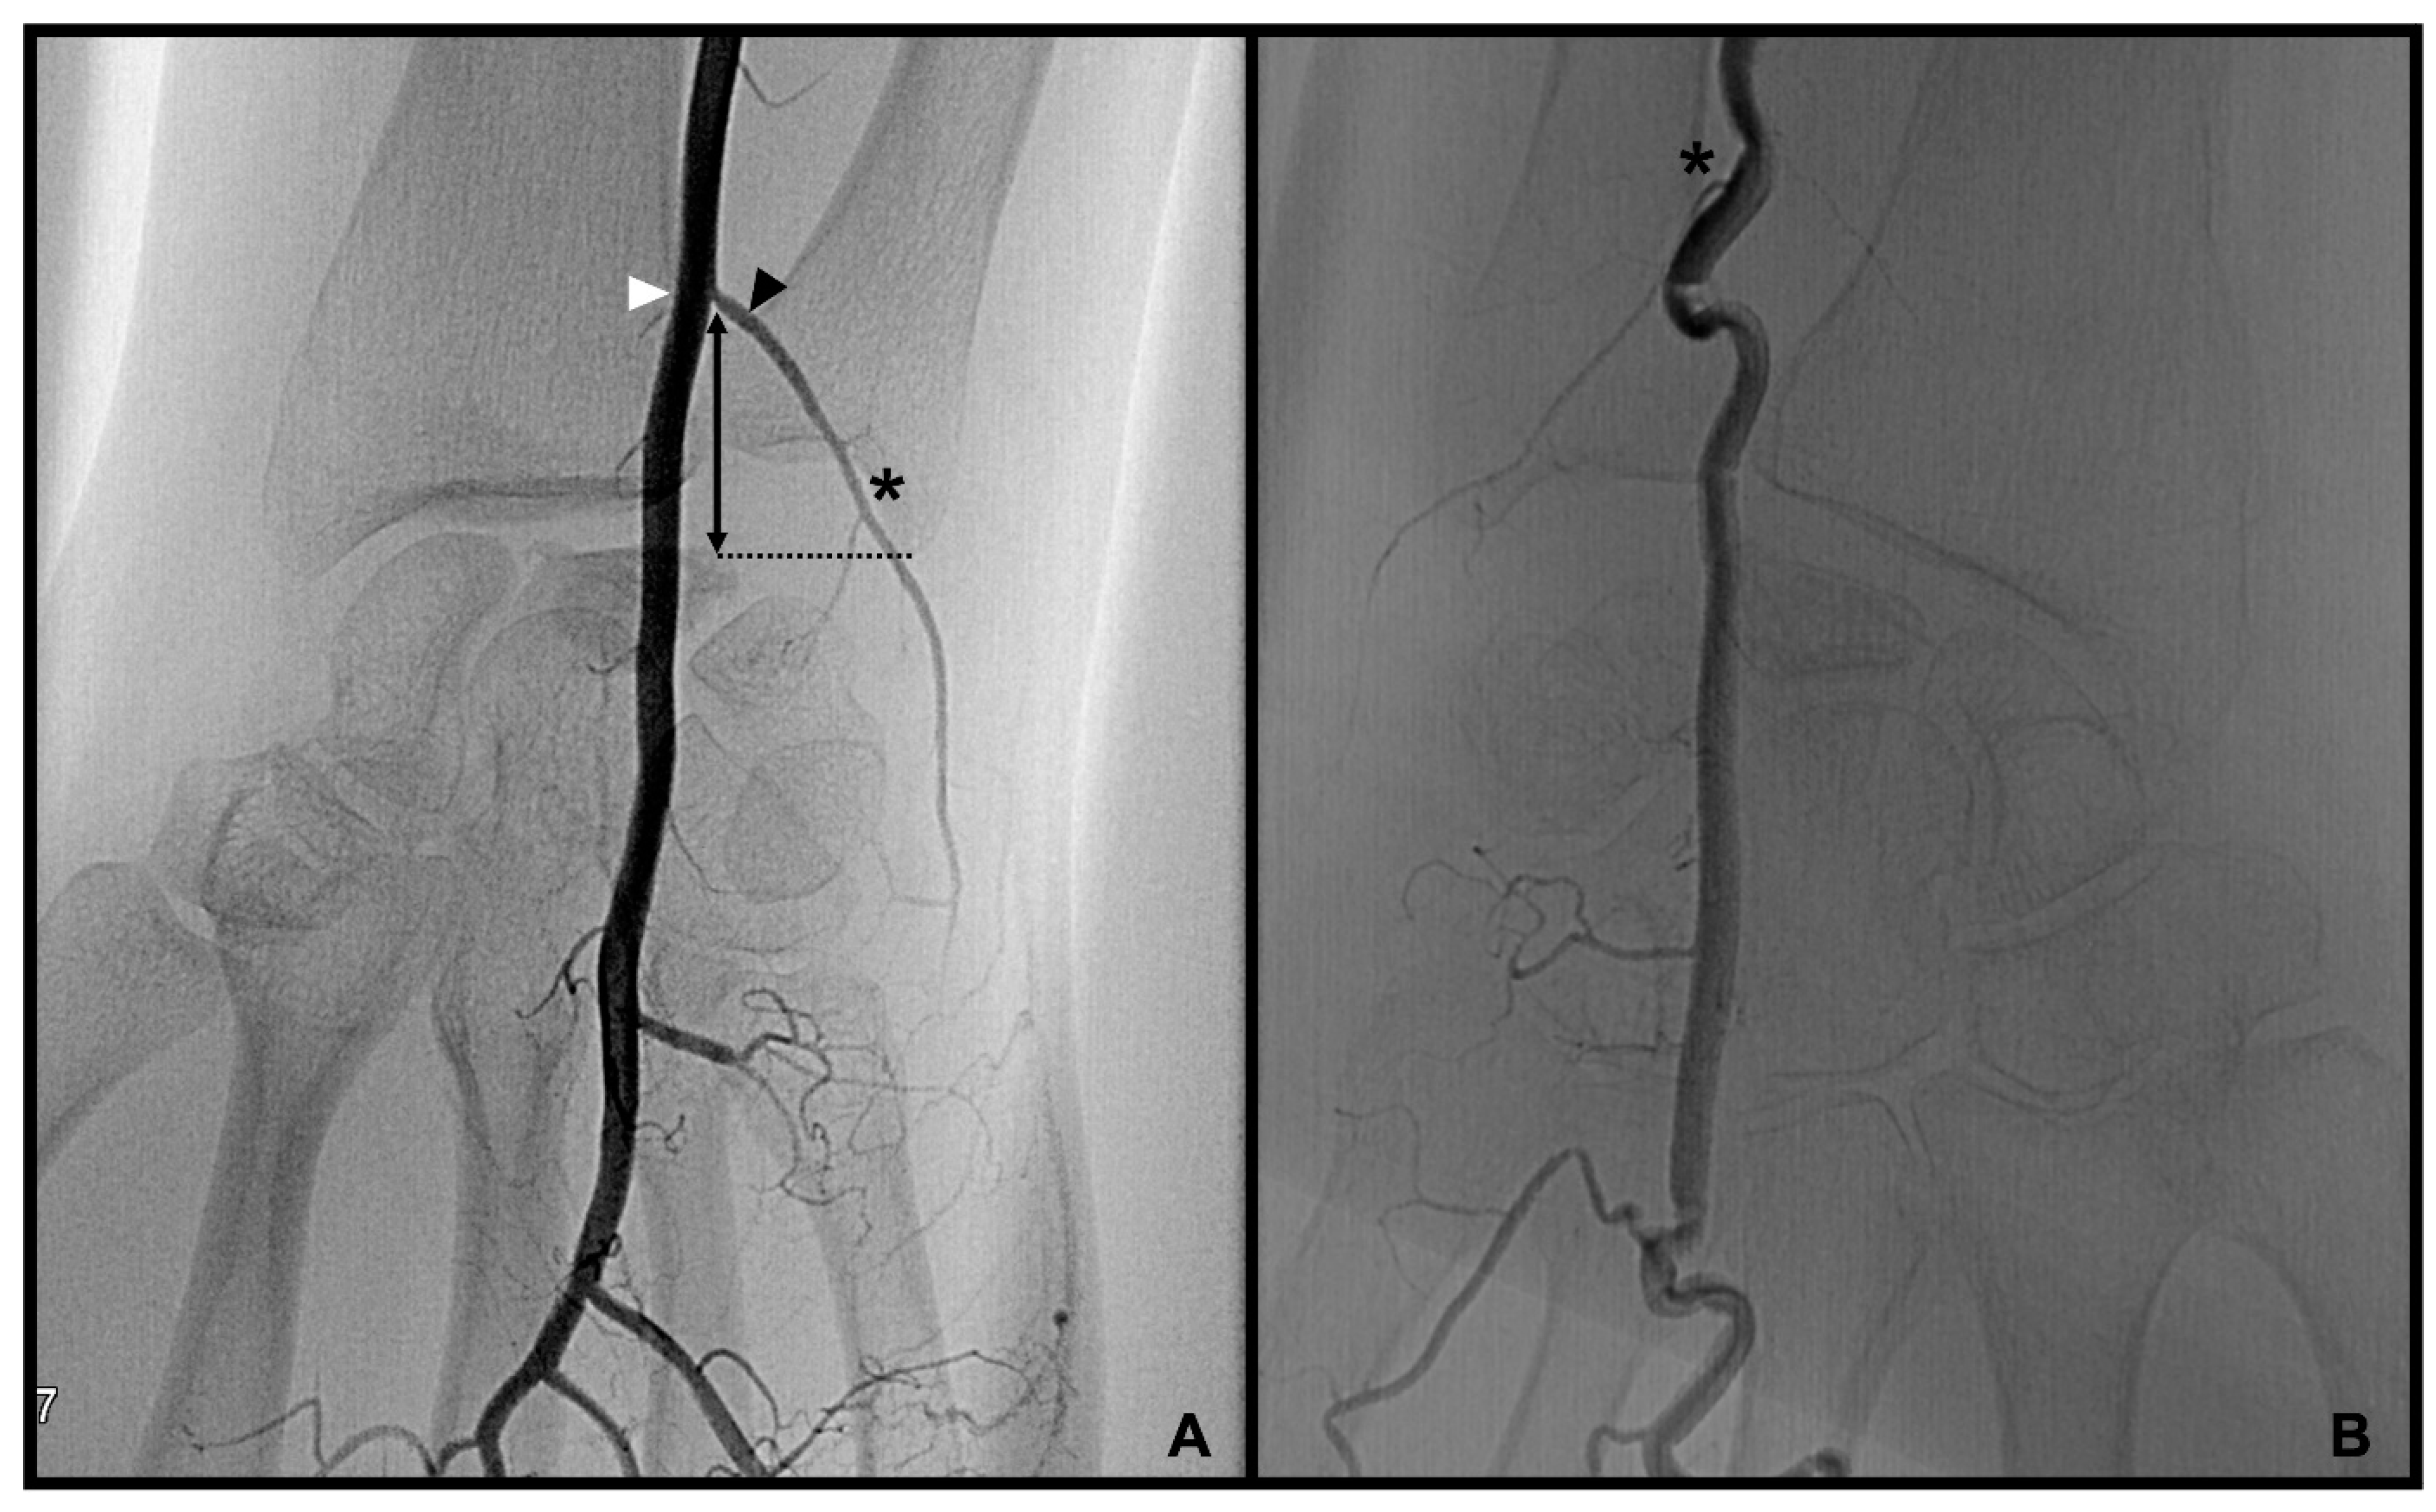

3.1. Palmar Radiocarpal Artery and Palmar Radiocarpal Arch (PRCA)

3.2. Dorsal Carpal Branch of the Ulnar Artery (DCBUA)

distance from the DCBUA to the styloid process of the ulnar (DCBUA = dorsal carpal branch of the ulnar artery).